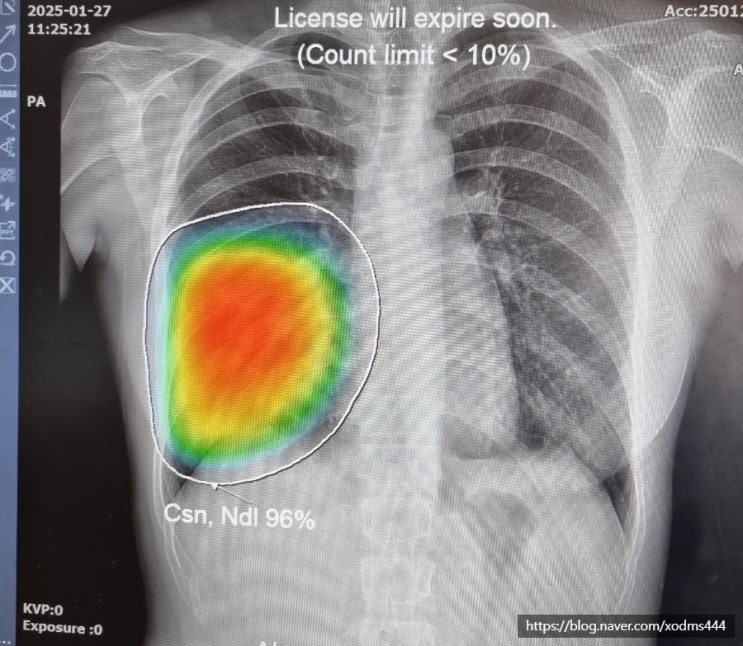

20대 폐렴 엑스레이 치료 후기 초기 증상 입원치료 기간

올해 초 쯤.. 폐렴에 걸렸다. 만 20대 후반이지만 아직 그래도 20대인데.. 폐렴에 걸렸다는 것이 너무나도 ...